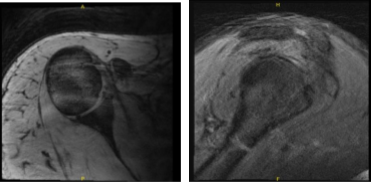

He came into our office with recurrent right shoulder recurrent pain which has not been getting better. The patient was weak in his rotator cuff muscles. The patient presented an MRI result and showed that it was normal but there was a high suspicion of rotator cuff tear.

MRI-3T Right Shoulder non-contrast